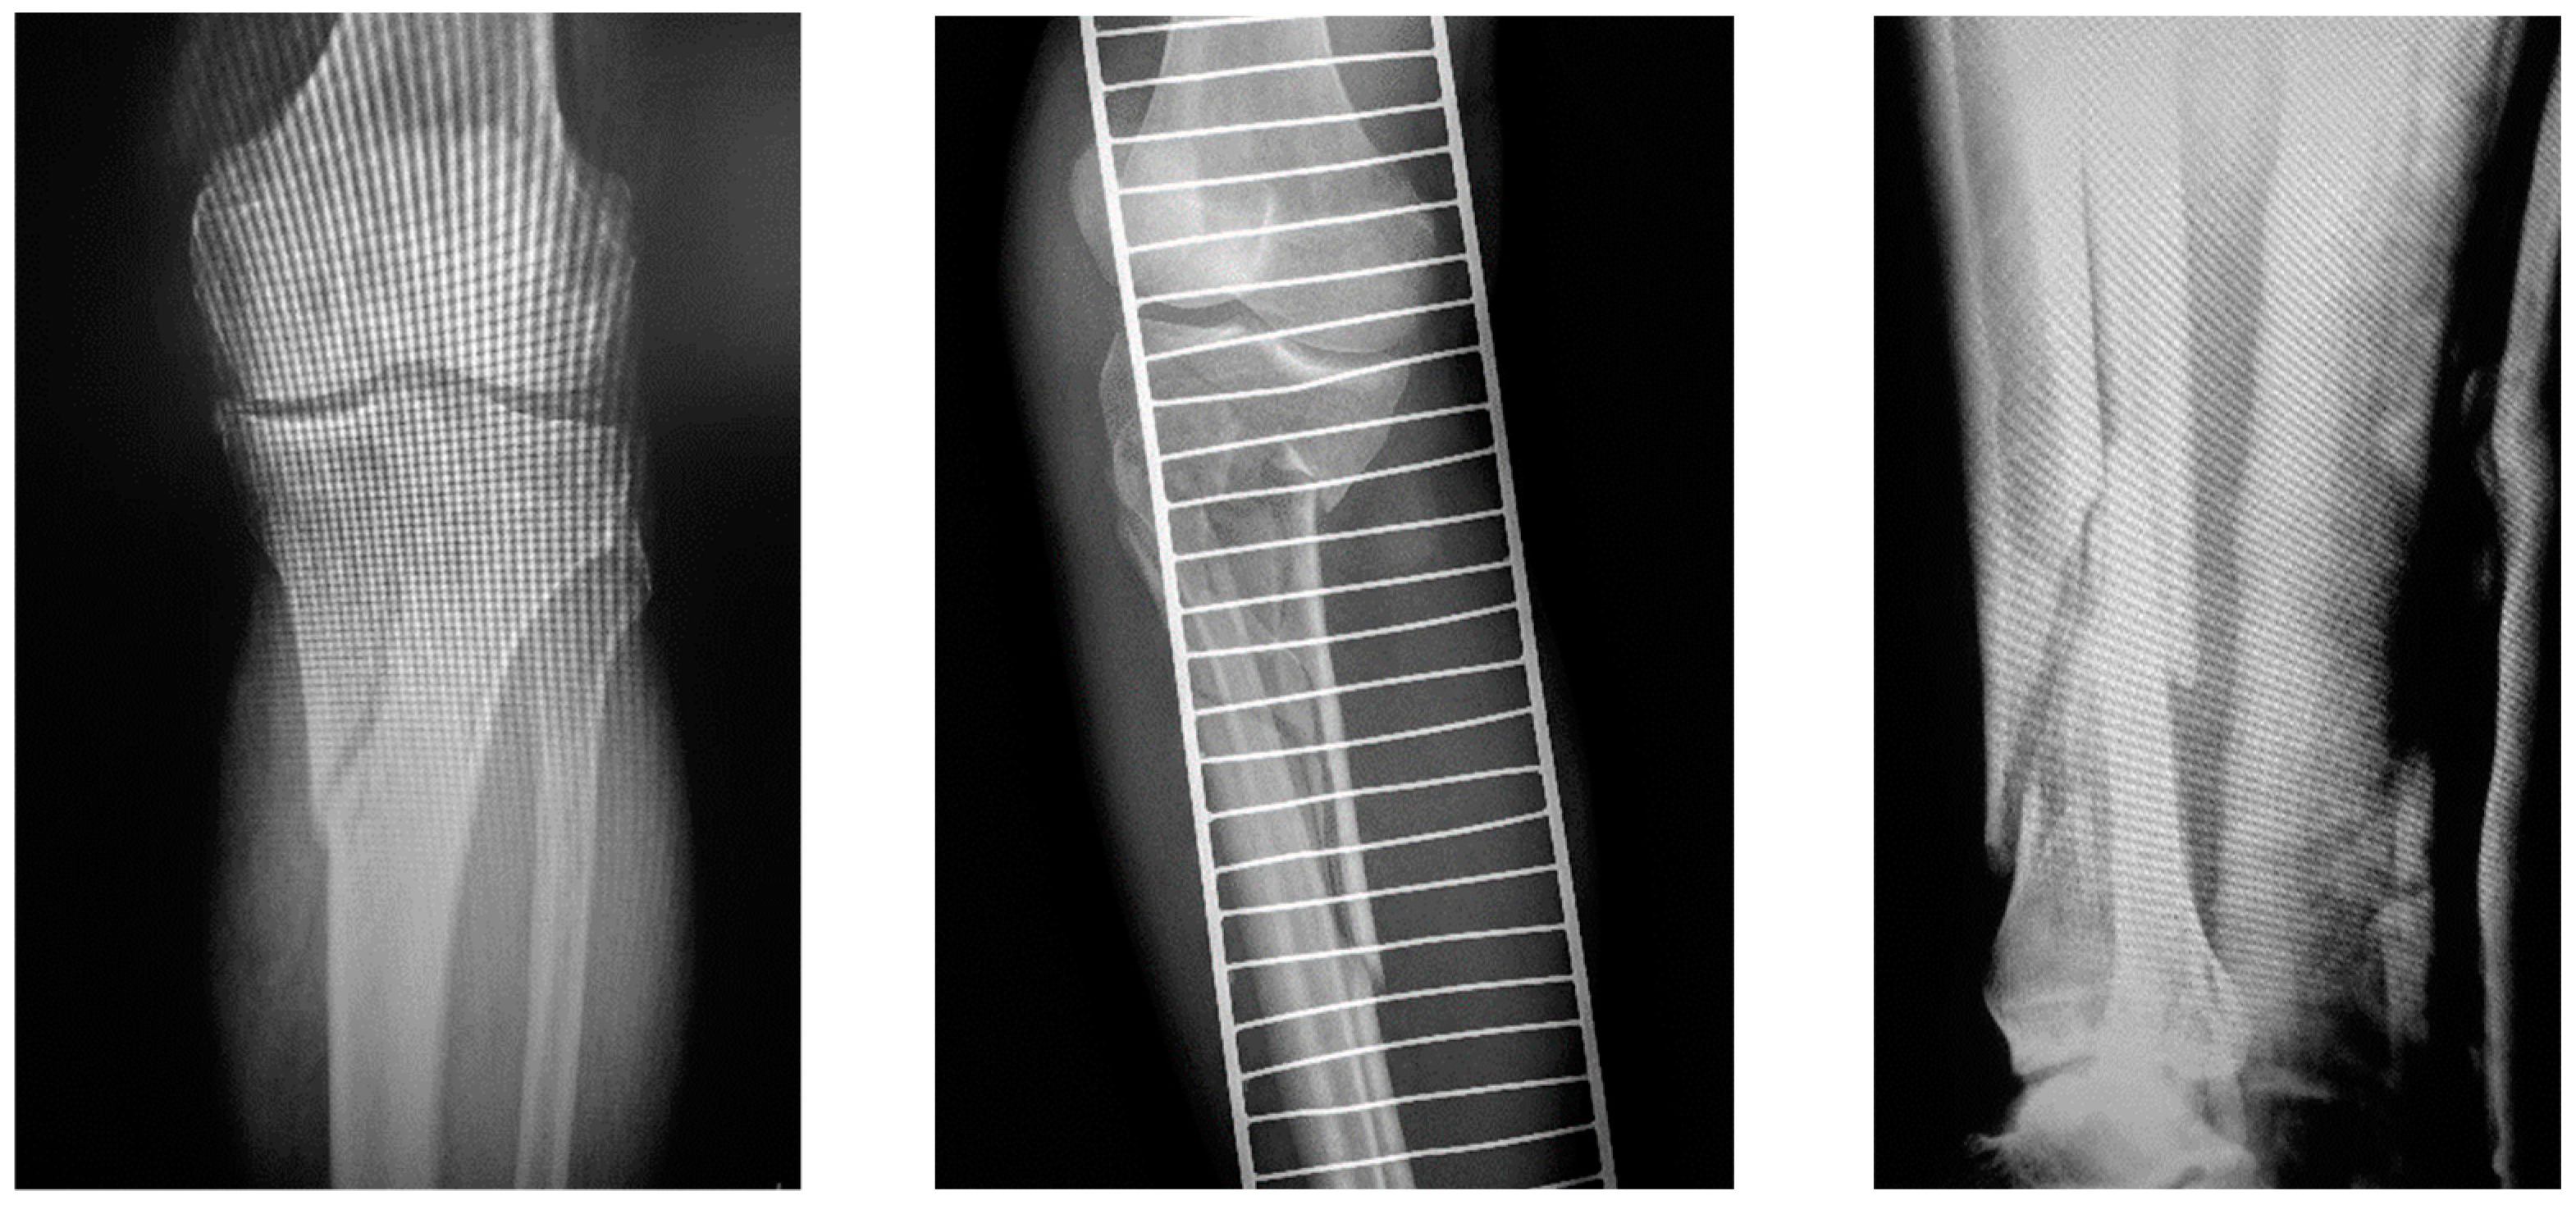

2.2. Surgical Technique

2.2.3. Single-Stage Externalized Locked Plating